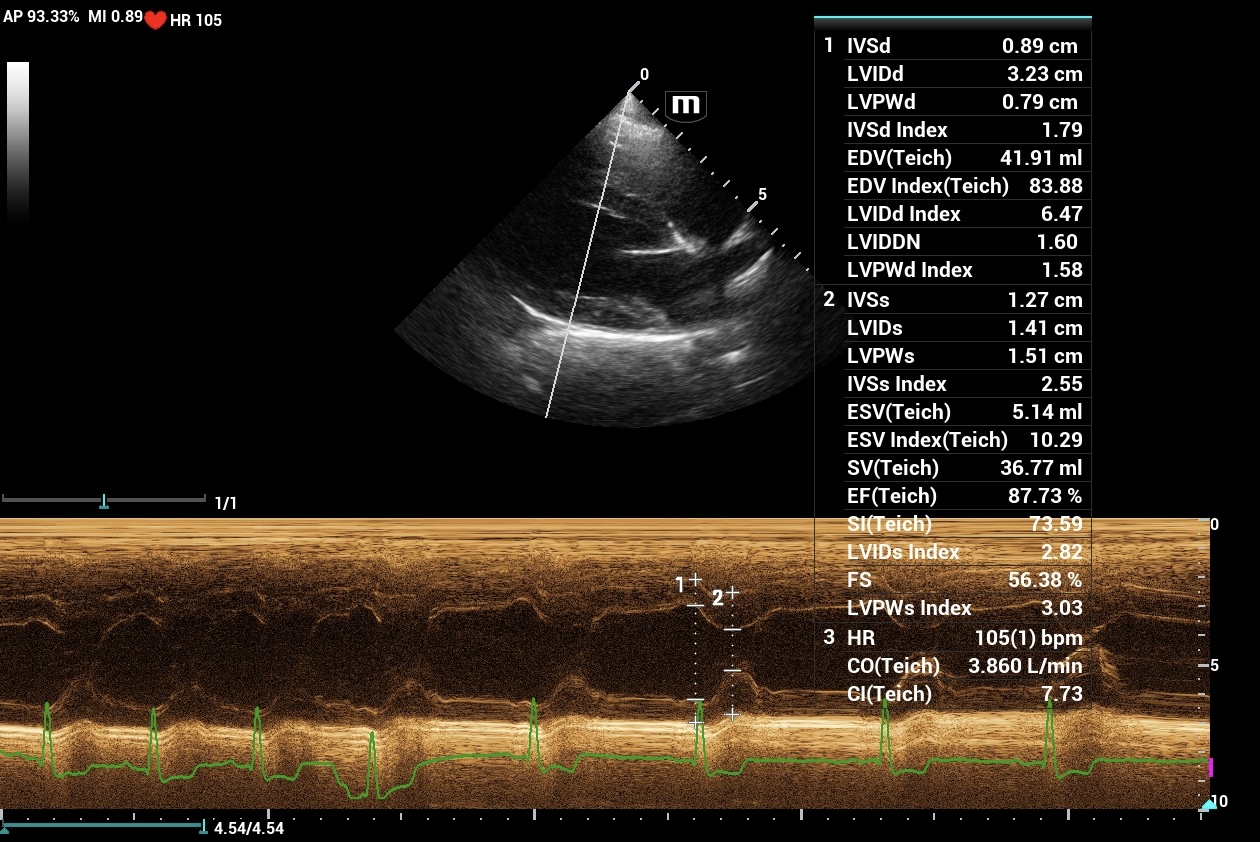

14Kg KCCS Dog; 3/6 murmur placed on Pimo after rads. Echo(3 wks later) revealed mild mod MV reg, TV reg and AO ins. PG – MV and TV=N. AO PG=N with plateau flow profile. Echo = stage B1 MVD, BP= N.Dog was 5 lbs ovweight. C index adj. to 11.7Kg= N.

Q: Could Pimo use be + affecting the LV size?